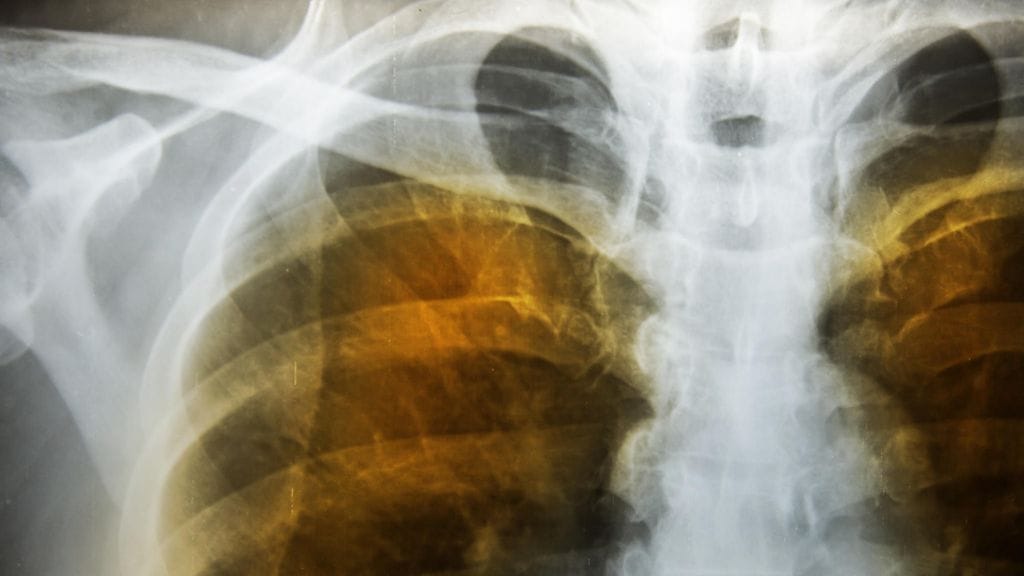

Tuore laaja yhdysvaltalaistutkimus osoittaa, että pitkäaikainen altistuminen ilmansaasteille ja erityisesti alailmakehän otsonille on vahvasti yhteydessä kohonneeseen riskiin sairastua emfyseemaan eli keuhkolaajentumaan.

Tutkijat vertaavat tiedotteessa ilmansaasteiden vaikutusta tupakointiin. Jos ihminen asuu alueella, jossa alailmakehän otsonitasot ovat korkeat, hänen riskinsä sairastua emfyseemaan on sama kuin ihmisellä, joka on polttanut askillisen tupakkaa 29 vuoden ajan.